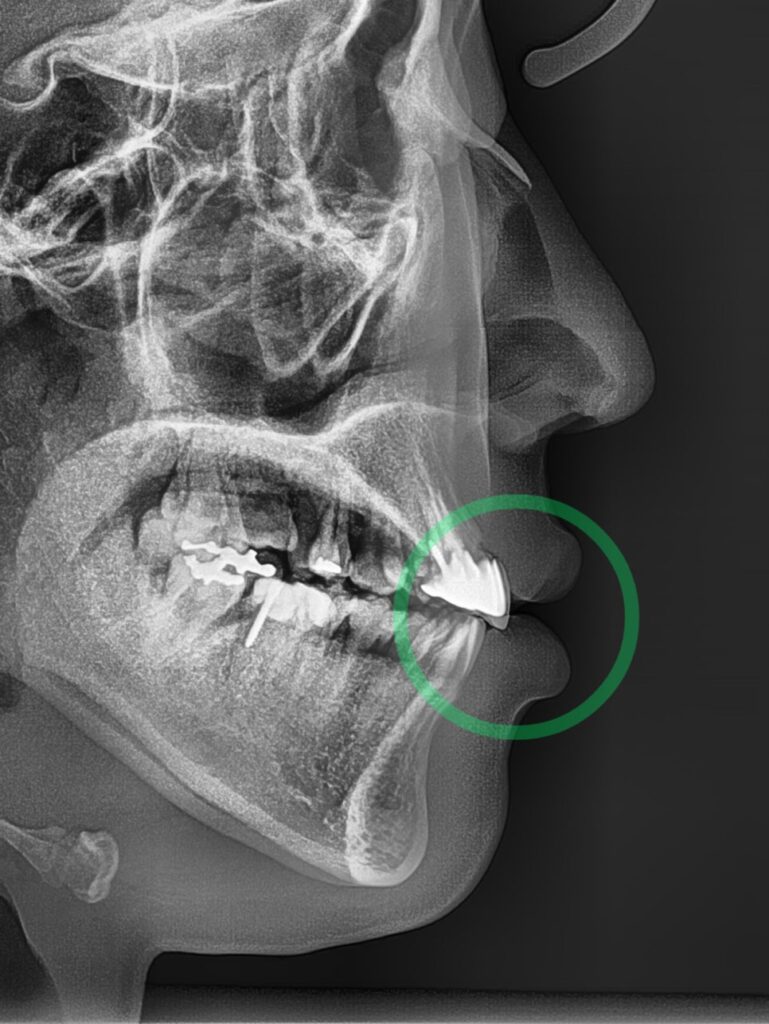

측면 세팔로 사진에서는 툭 튀어나오고

뻐드러진 앞니 때문에 입을 다무는 것이

쉽지 않아 보였습니다.